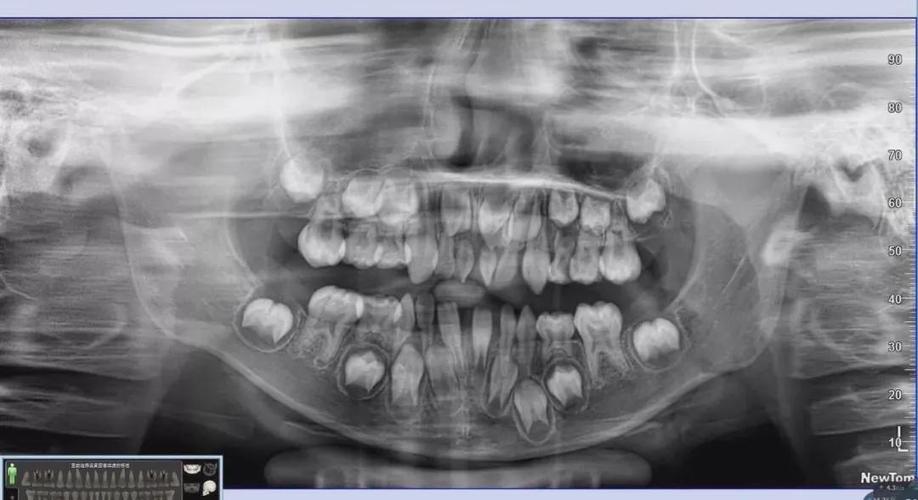

小孩牙齿x光图,小孩牙齿图片恒牙图片

看牙齿的x光片如何看出牙齿是恒牙还是乳牙?

牙齿的牙根是埋在牙槽骨中的 医生没有透视眼 为了解患牙的牙根的

健康牙齿图片x光图片

正常儿童牙齿x光图

儿童换牙x光图

正常牙齿的x光拍片图

正常牙齿咬合图x光